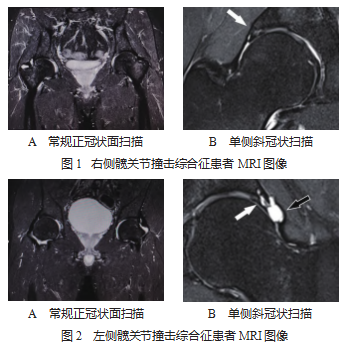

2.3 MRI 诊断髋关节撞击综合征的影像学图片 患 者 1 ,男性,29 岁,2020 年驾驶汽车追尾后出现右髋部 疼痛;经 MRI 常规正冠状面扫描显示右髋关节腔少许 积液, 见图 1-A ;斜冠状位图白箭指示上盂唇连续性欠 佳,可见高信号影改变,考虑右髋关节上盂唇损伤,见 图 1 -B。患者 2 ,男性,68 岁,2019 年起发现左髋部疼 痛,经保守治疗缓解后进行活动,突发左侧髋部疼痛;经 MRI 常规正冠状面扫描显示左髋关节腔积液增多,局部 成囊状,关节盂未见明显异常,见图 2-A ;斜冠状位白 箭指示左髋上盂唇局部不连,诊断左髋关节上盂唇撕裂, 见图 2-B。